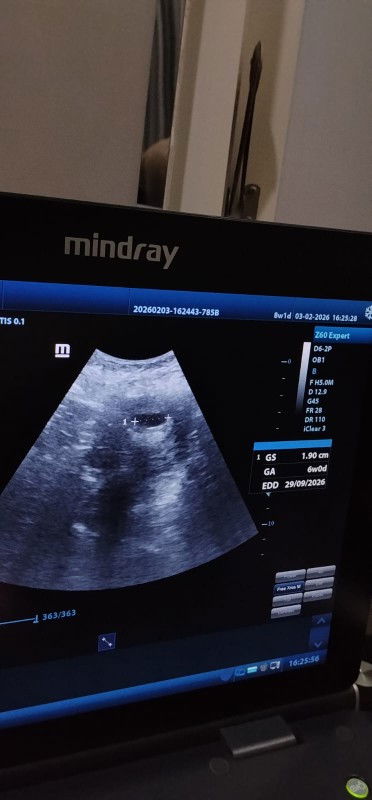

Bund.. USG 6weeks

USG 6weeks Bund.. USG 6weeks masih keliatan kantung nya ... Normal kah bund ?? Semoga lekas ada janin djj dan ibu sehat selalu.. aamin

Hihi bund smaan kaya aku ,td pagi aku usg usianya 6w1d bru keliatan kantungnya aja edd 30 september 2026 ,kl menurut HPHT uknya 5w4d itu edd 04 oktober 2026 Normal kok bund dlu ak anak kedua usg pas 6w1day jg baru keliatan kantung aja ,ini kehamilan ke tiga seht selalu utk kita semua ya bun ,bunda dan debay yg ada diperut kitaa🤗🥰🥰

Baca laginormal kok. saya juga waktu USG pertama usia kandungan 6week baru terlihat kantong sebesar 2cm. minggu depannya cek lagi di usia 7w sudah terlihat janin dan detak jantung. alhamdulillah, sekarang anaknya sudah lahir dengan sehat semangat bunda, jangan lupa minum vitaminnya.